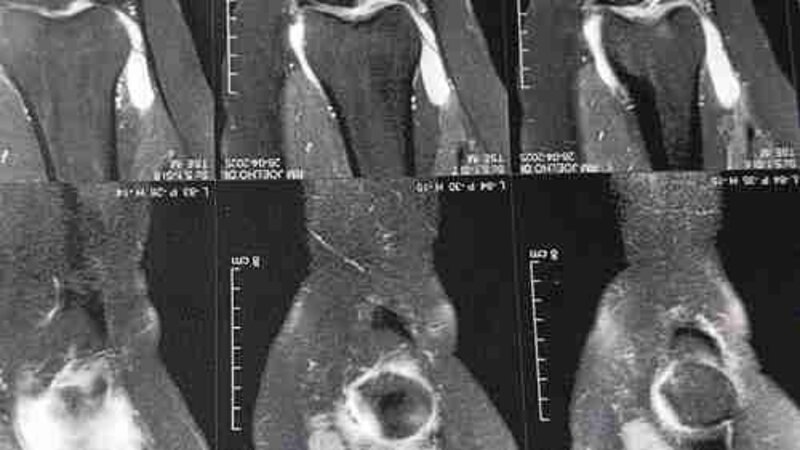

Ola,me chamo Manuela, tenho 39 anos e estou precisando de ajuda para fazer uma cirurgia no joelho direito e tratamento no joelho esquerdo e na coluna. Estou há 2 anos sofrendo com dores difíceis de suportar, procurei ajuda pelo Sus, mas nunca havia vaga para um cirurgião ortopedista especializado acompanhar o meu caso. Nesse período, descobri que estava com um cisto chamado de Cisto de Baker. Esse cisto está associado à condição na qual me encontro, com artrite reumatoide e lesões de menisco. Como o cisto não está respondendo ao tratamento e está grande, precisa fazer a cirurgia. Estou também com uma doença degenerativa chamada Gonartrose que causou a degeneração da cartilagem do meu joelho, fazendo uma fratura, aonde precisa da cirurgia (substituição da articulação ou prótese do joelho) para recuperação, pois está me impedindo de caminhar. Devido à Fibromialgia, as dores no corpo aumentam consideravelmente. Precisei fazer um plano de saúde para acompanhamento, tratamento e cirurgia. Mas sou sozinha, dependia do meu trabalho para pagar aluguel e contas básicas de casa e, o principal, o plano de saúde. Devido aos vários problemas aos quais me encontro, o servidor público retirou as minhas aulas e estou desempregada, precisando urgentemente dessa cirurgia para me recuperar e voltar a procurar emprego. Preciso, além das necessidades básicas, de dinheiro para continuar pagando o plano de saúde, pelo menos até fazer a cirurgia, medicação e uma cadeira de banho. Para voltar a caminhar. Por isso estou aqui hoje contando com seu apoio e ajuda no que puder ajudar, serei eternamente grata, e Deus há de retribuir todo bem que vocês puderem fazer. Abaixo deixo as fotos da coluna e joelho. Que Deus abençoe grandemente a cada um que puder contribuir, juntos somos mais fortes. Um forte abraço e muita gratidão.